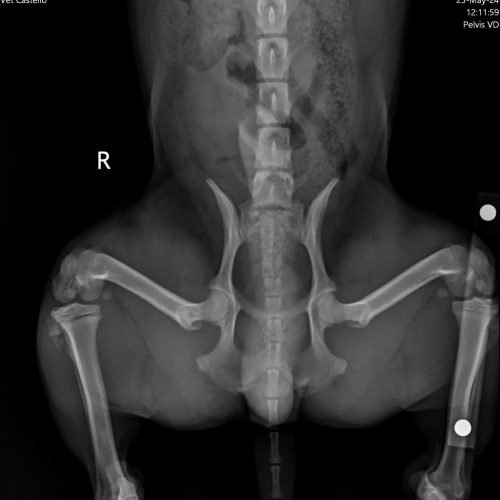

A ortopedia em cães e gatos é uma especialidade veterinária que se dedica ao diagnóstico e tratamento de doenças e lesões do sistema musculoesquelético, que inclui ossos, articulações, músculos e ligamentos. Problemas comuns nessa área incluem fraturas, luxações, displasia coxofemoral da anca e artrite.

Os sinais de problemas ortopédicos podem incluir claudicação, dor, dificuldade para se mover e mudanças no comportamento. O diagnóstico geralmente envolve exames físicos, radiografias e, em alguns casos, ressonância magnética.